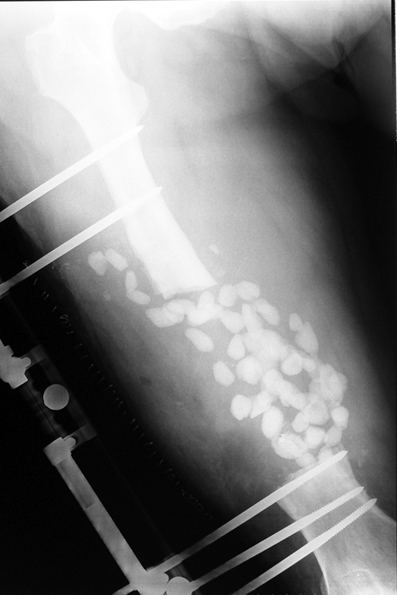

Chronic osteomyelitis leads to necrosis of bone and soft tissues. Dead bone is a nidus which hosts pathogenous microorganisms. Defence mechanisms of the host is usually not in optimum condition to deal with microorganisms. Antibiotics can’t reach the infection site because blood flow is disrupted. For these reasons, dead bone has to be completely removed by radical debridement.

Appropriate radical debridement necessitates excision of all necrotic bone and soft tissues, and frequently causes instability at the involved extremity. The remaining bone and soft tissue defect has to be fixed and reconstructed. The distraction osteogenesis method of Ilizarov is used successfully for achievement of union, correction of the deformity, elimination of limb length inequality and reconstruction of segmental bone defects.

The duration of external fixation (external fixation index) depends on the amount of distraction required, and the extremity is prone to complications during this period. After the distraction phase is completed, the external fixator remains in place during the consolidation phase, which lasts twice as long as the distraction phase; but this period is hardly tolerated. If the external fixator is removed before sufficient consolidation is achieved, fractures, deformity and shortness will be the result. In our department, ‘lenghthening over nail’ method is used in order to decrease the external fixation index and increase patient comfort and activity level. In this method, the intramedullary nail is statically locked after the completion of the distraction phase, and external fixator is removed. The extremity is stabilized by the intramedullary nail during consolidation phase. In this way, complications due to long external fixation index or early removal of the external fixator are avoided.